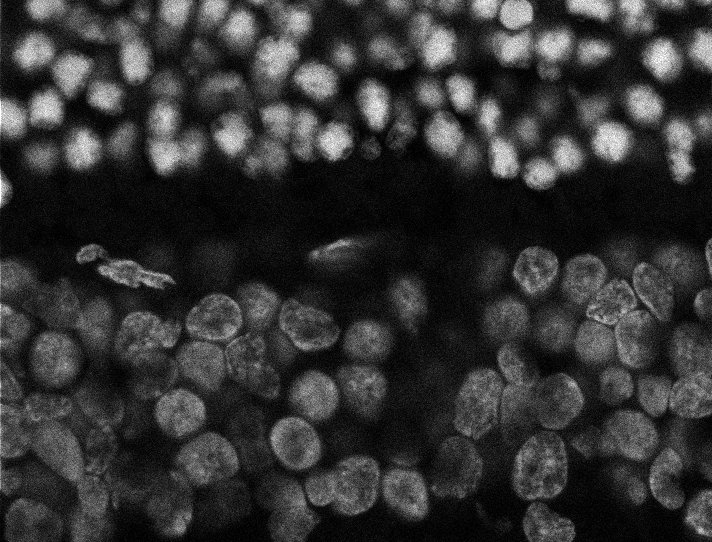

Nuclei